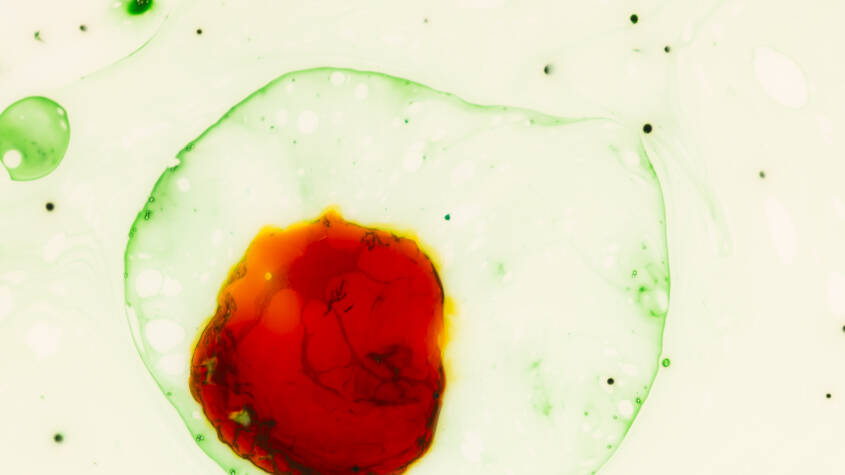

The researchers found changes in the quantity, size, volume, and function of red blood cells in the population exposed to mercury contamination, which can lead to anaemia. Changes in other biomarkers also indicate damage to organs such as the liver and kidneys. Mercury was found to increase triglyceride levels, which are a risk factor for cardiovascular disease. Additionally, creatinine and urea levels were high in the contaminated population, suggesting kidney dysfunction.